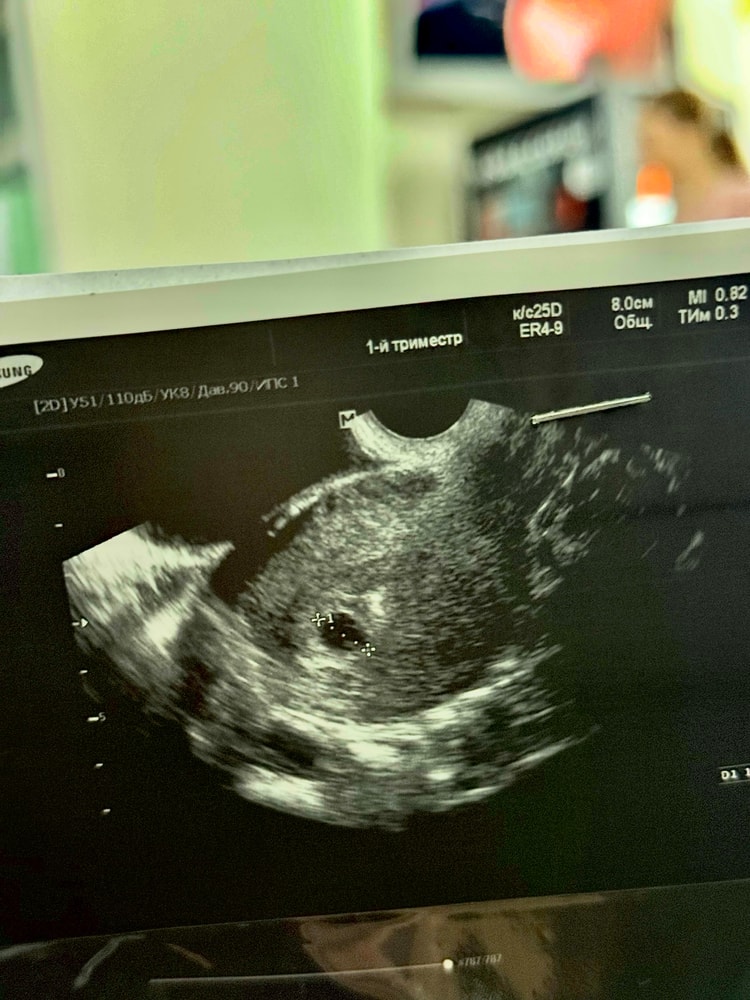

Ангелина, в заключении плодное яйцо 11мм жм 3мм

Юлия, она мельком меня посмотрела, ничего не сказав,написав в заключение, беременность 5нед и все😂 а я сижу и разглядываю и гадаю

Если бы было 2 жм то в заключении так и написали бы, указав размеры обоих жм. А поскольку у вас указан 1, то он там 1, не стоит разглядывать эти фотки.

я не вижу два ... думается один